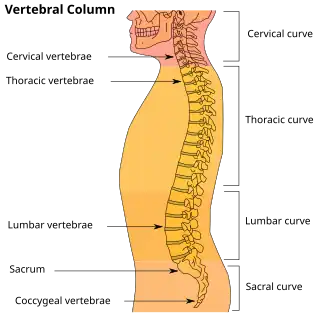

Regiunea lombară constă în cinci vertebre (L1-L5). Între acestea se află discuri fibrocartilaginoase, care acționează ca niște perne, împiedicând frecarea intervertebrală și protejând măduva spinării. Nervii vin de la și se îndreaptă către măduva spinării prin intermediul canalelor specifice dintre vertebre, dând pielii simțul tactil și trimițând mesaje mușchilor. Stabilitatea coloanei este dată de ligamentele și mușchii spatelui și abdomenului. Articulațiile mici, denumite articulații fațetare, limitează și controlează mișcarea coloanei.[12]